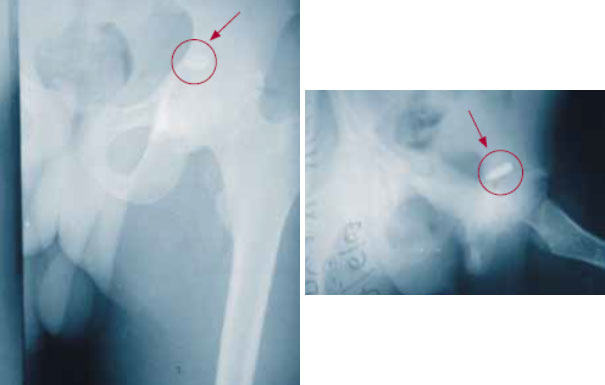

Очевидно, что если в процессе иссечения раны хирург обнаружит ранящий снаряд, то он должен его удалить. Однако не следует рассекать здоровые ткани в поисках такого снаряда. Тем не менее есть два условия, при которых требуется немедленное удаление пуль и осколков, и эти условия связаны с подтвержденными практикой рисками и осложнениями.

Рисунок 3. Пуля в тазобедренном суставе

Проводить ли удаление в срочном или плановом порядке, будет зависеть от анатомической локализации инородного тела и от того, какая структура подвергается опасности, от гемодинамической стабильности пациента, наличия диагностического и операционного оборудования и, что самое важное, от квалификации хирурга. Риски, связанные со сложной процедурой (удалением пули из средостения, головного мозга и т. д.), при которой процент осложнений может быть весьма высоким (особенно в неопытных руках), необходимо сопоставить с преимуществами отказа от такой процедуры, имея в виду, что общая частота осложнений при отказе низка. Более подробно показания к удалению будут рассмотрены отдельно.